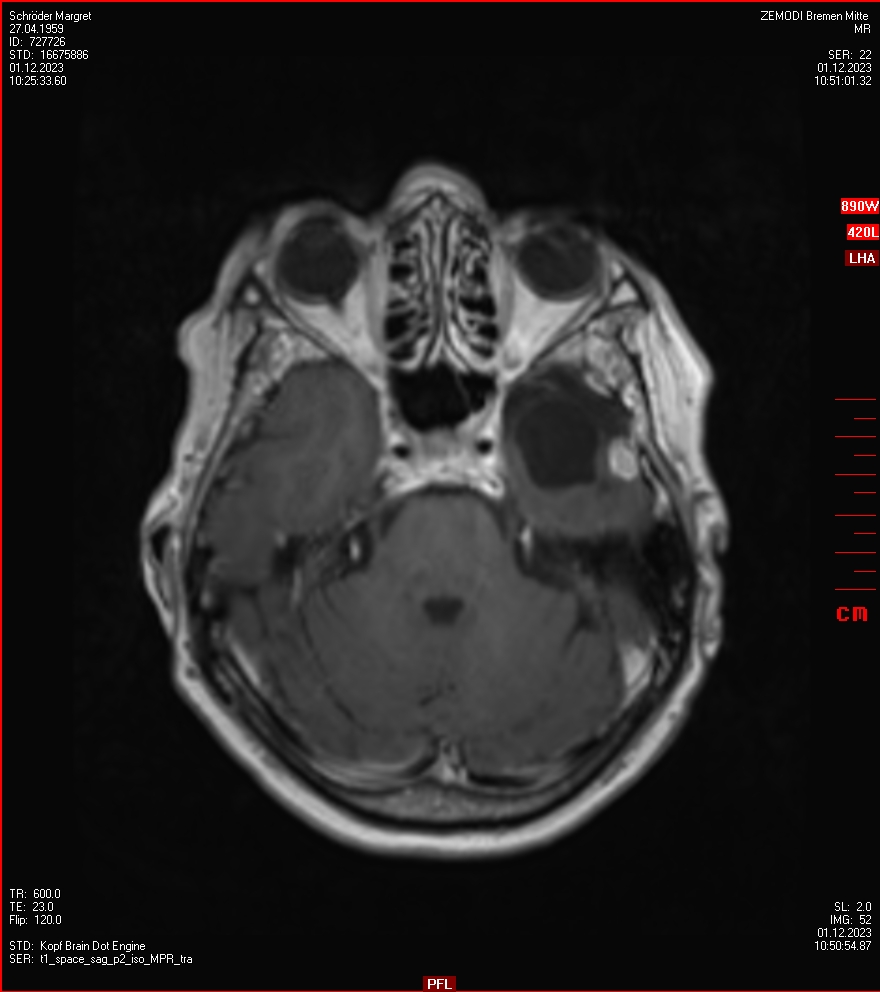

Die letzten drei Bilder Zeigen aus meiner Sicht den Tumor, der im Jahr 2021 bestrahlt wurde.

Zum Vergleich nun auch die Bilder vom 1.12.2023: